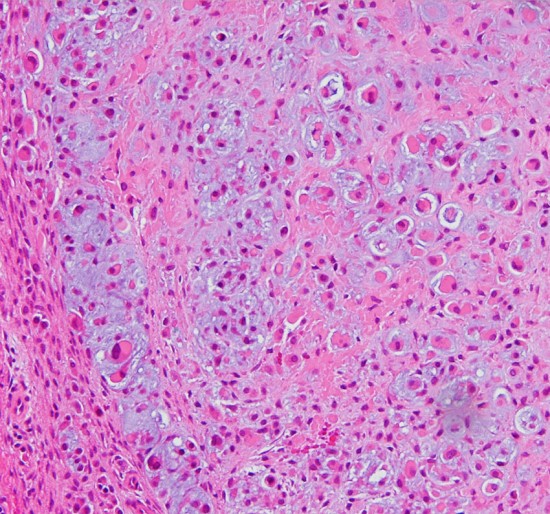

病理

低悪性度軟骨肉腫の病理像 grade 2 chondrosarcoma

背景は好塩基性の軟骨基質(粘液状 myxoid,軟骨様 chondroid)です。好酸性胞体をもつ異型紡錘形ないし上皮様細胞が多結節状に増殖しています。細胞密度はやや高い部分もあり,核は濃縮され大小不同や2核の細胞も見られます。MIB-1 index 3%